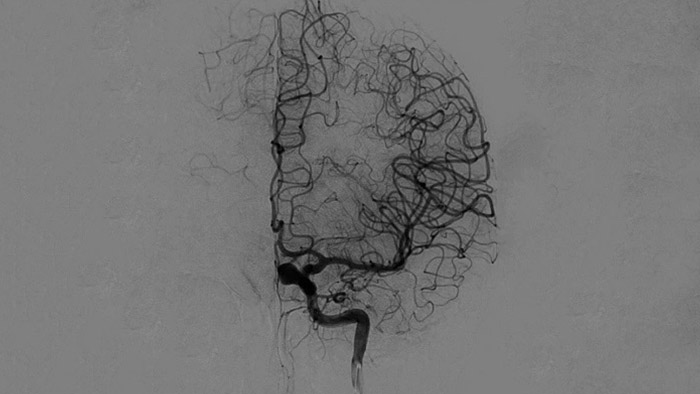

ClarityIQ applique la compensation automatique des mouvements lors de l’angiographie par soustraction numérique (ASN) en temps réel pour maintenir la netteté des images des vaisseaux et contribuer à une prise de décision fiable tout au long des procédures d’AVC.

Visualisation d’angiographie par soustraction numérique (ASN)

Les visualisations d’angiographie par soustraction numérique (ASN) de haute qualité vous permettent d’évaluer si vous avez retiré le caillot complet et si des morceaux de caillot ont été dispersés de manière distale dans le cerveau. Vous pouvez vérifier le rétablissement du débit sanguin dans la pénombre et contrôler les hémorragies péri-procédurales.